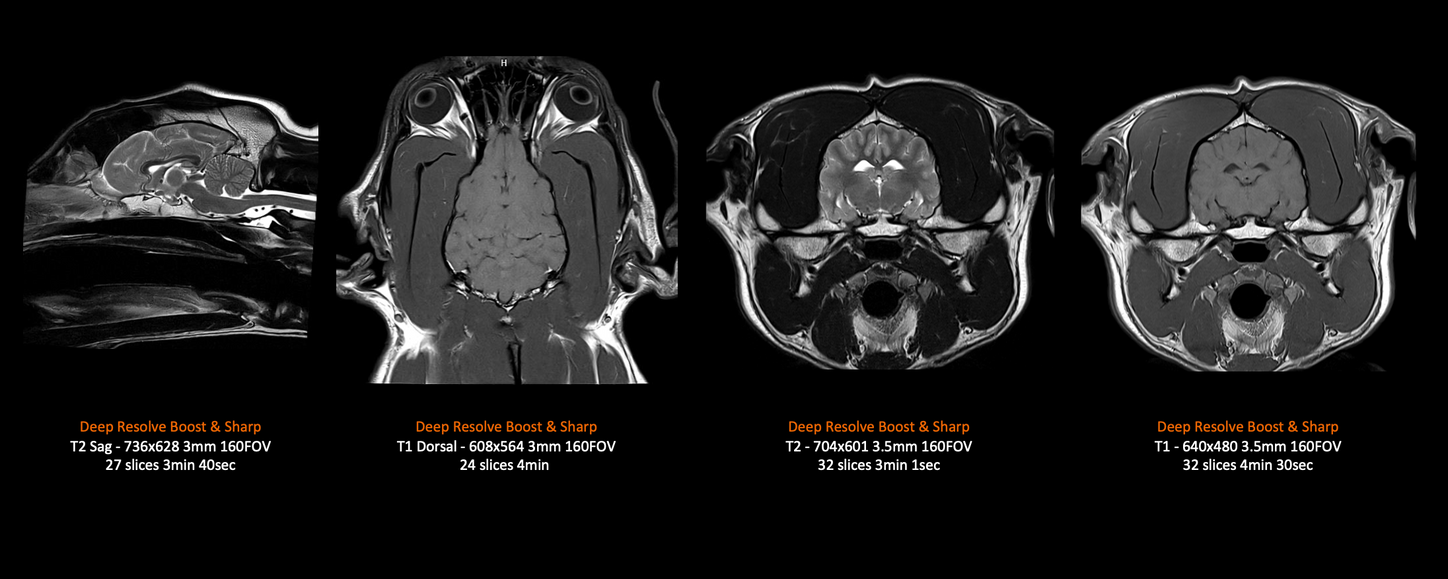

MAGNETOM Flow – 2kg Dog Brain (Contour Small)

Deep Resolve Boost and Deep Resolve Sharp

Images courtesy of Animal Referral Centre, Auckland, New Zealand

MAGNETOM Flow – 30kg Dog Brain

Images courtesy of Case ID Study ID: UK_MAC_1aaaa5968